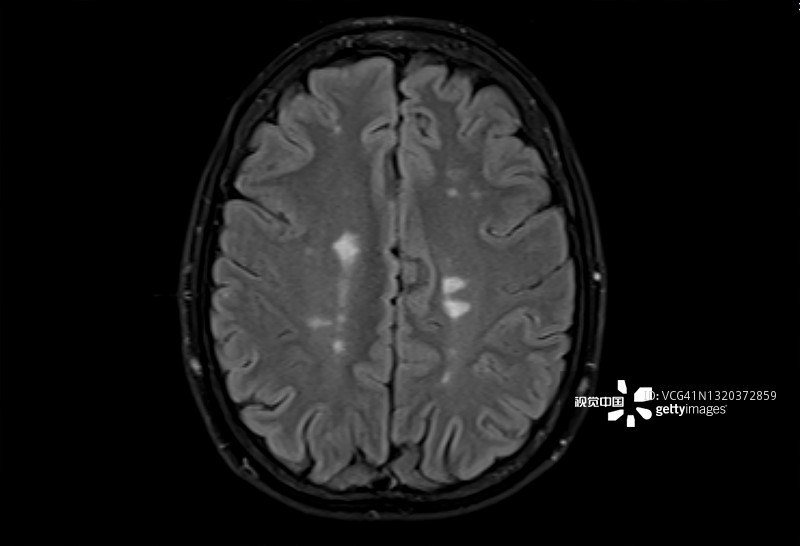

多發(fā)性硬化癥 (MS):MS是一種中樞神經(jīng)系統(tǒng) (CNS) 的慢性自身免疫和炎癥性疾病。MS與免疫系統(tǒng)介導(dǎo)的自身反應(yīng)性T細(xì)胞和B細(xì)胞對(duì)神經(jīng)元髓鞘的攻擊有關(guān),導(dǎo)致脫髓鞘并最終導(dǎo)致神經(jīng)元丟失。由于中樞神經(jīng)系統(tǒng)中神經(jīng)變性和斑塊的形成,MS患者會(huì)根據(jù)斑塊的位置經(jīng)歷特定的神經(jīng)功能障礙。例如,視神經(jīng)中的斑塊會(huì)導(dǎo)致視力喪失。